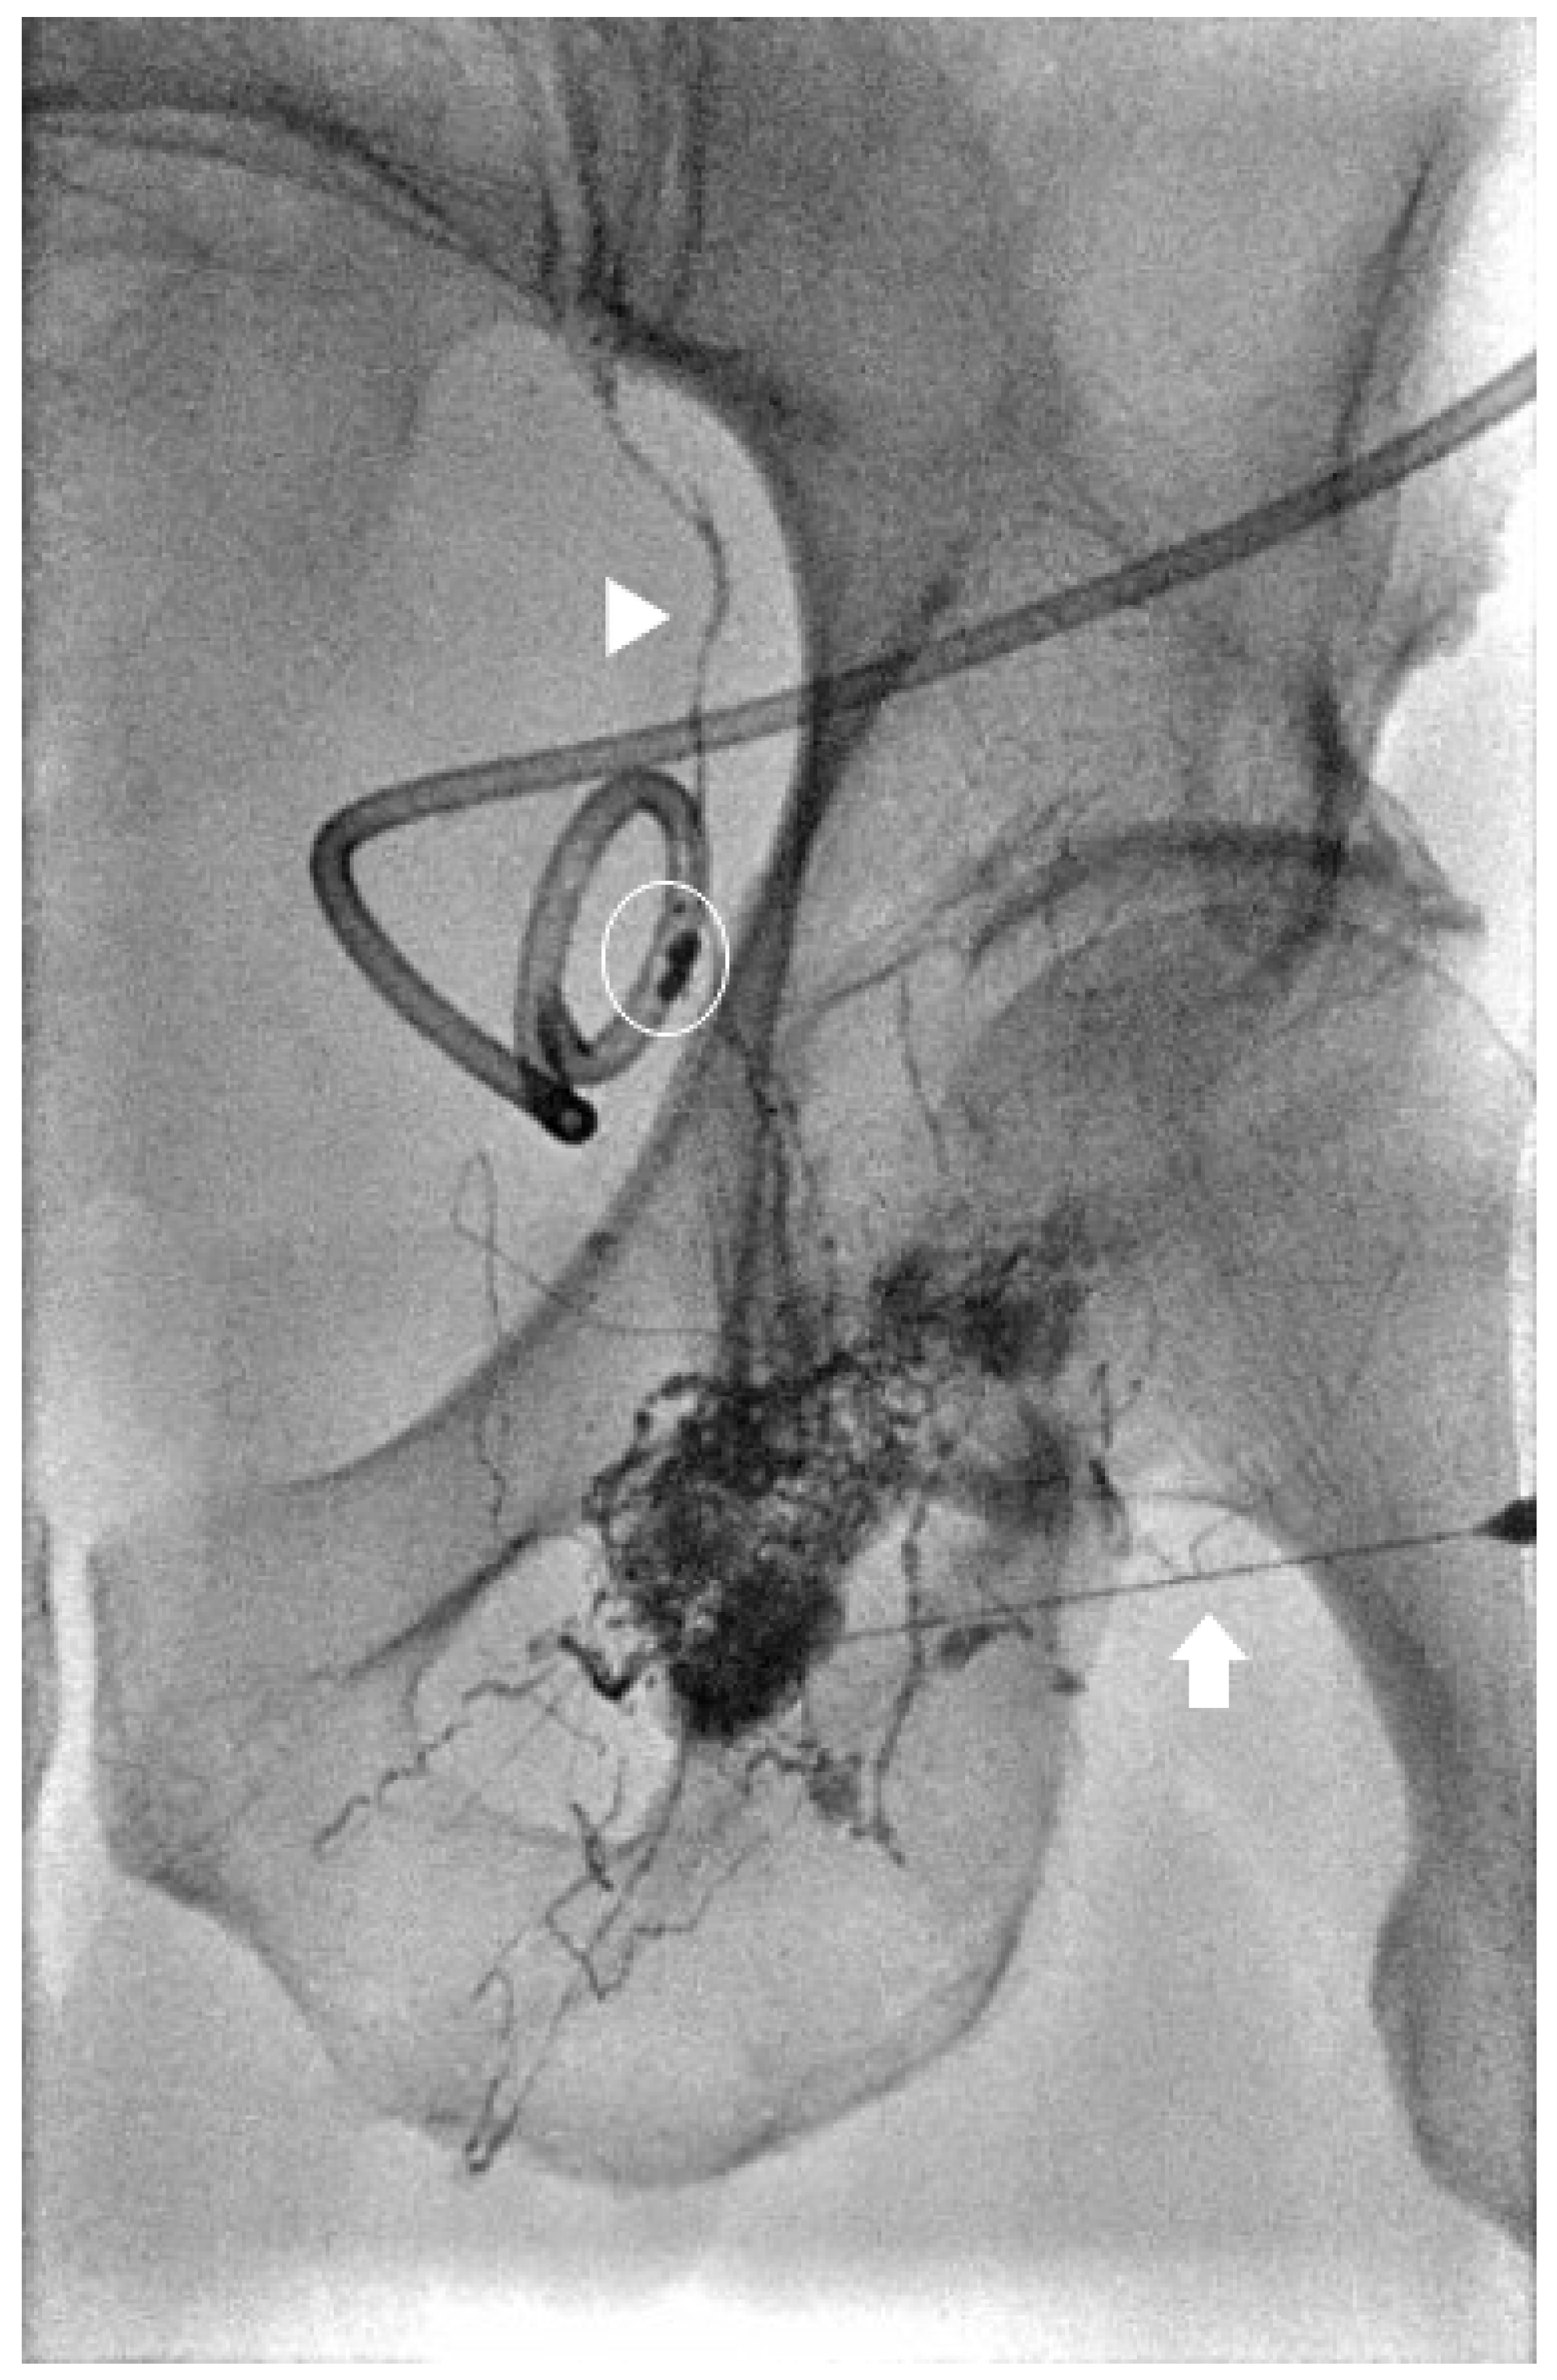

Lymphoceles, defined as walled-off collections of extravasated lymph, can occur anywhere in the body after lymph node dissection and typically require intervention only when symptomatic. While various management strategies exist, including sclerotherapy and surgical approaches, recent evidence suggests that lymphangiography with or without lymphatic embolization (LE) may offer superior outcomes. Moussa et al. conducted a comparative study of 46 patients, demonstrating that intranodal lymphangiography with LE resulted in shorter post-intervention drain dwell times (median 6 days vs. 13 days), higher initial clinical success rates (83% vs. 47%), and fewer procedures for resolution compared to sclerotherapy (Figure 5 and Figure 6) [33]. Similarly, Seyferth et al. reported that lymphangiography with intranodal glue embolization (IGE) achieved comparable clinical success rates to sclerotherapy (15/18 vs. 15/23), but with fewer mean intervention sessions (1.3 vs. 2.5) and significantly reduced mean time to resolution (7 days vs. 27 days) [34].

Figure 6.

Spot image from an intra-nodal lymphangiogram for the same patient in Figure 5 showing a 25-gauge needle within a left inguinal lymph node (arrow) and lipiodol within the lymphatic vessels (arrowhead). Lipiodol is seen leaking close to the indwelling pelvic lymphocele drain (circle) confirming the lymphatic leak.